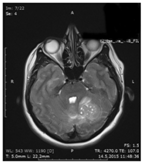

A 28 year-old female patient with long-lasting intermittent nausea was admitted to our hospital with the complaints of nausea, vomiting, and headache. The neurologic examination was normal with normoactive deep tendon reflexes. Cranial MRI revealed a hydrocephalus due to pressure on the 4th ventricle in the left cerebellum (Figure 1) and external ventricular drainage system was applied to the patient. Subsequent contrast-enhanced cranial MRI examination revealed, a massive heterogeneous contrast enhanced lesion which was iso-hypointense in T1 and iso-hyperintense in T2 imagings and located on the lateral left cerebellum and extended to the cerebellopontin angulus, showing compression to the 4th ventricular and extraaxial placement (Figure 2-4). The patient was operated, and the tumor in pink-gray colored, soft and flexible consistency was totally removed. She was followed by external ventricular drainage and the external drainage system was withdrawn with the normalization of Cerebrospinal Fluid(CSF) circulation. The postoperative course was uneventful and she was taken to the chemotherapy and radiotherapy program. At one month control no neurologic sequellea was observed.

Figure 2 In non-contrast cranial MRI a mass revealed to pressure on the 4th ventricle in the left cerebellum.

Figure 3 In contrast axial cranial MRI a mass revealed to pressure on the 4th ventricle in the left cerebellum.